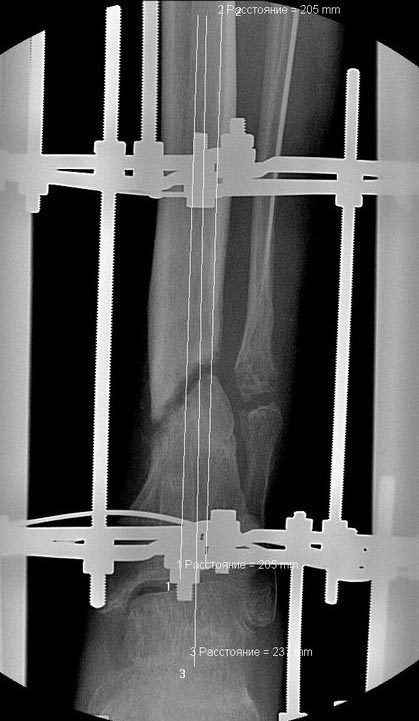

Уважаемые коллеги выразите Ваше мнение по следующему случаю.Молодой человек, 27 лет, находится на лечении с диагнозом: Ложный сустав большеберцовой кости в нижней трети, фиксированный интрамедуллярным блокированным стержнем (12.02.2014 г), ложный сустав малоберцовой кости в нижней трети левой голени, посттравматический артроз левого голеностопного сустава 1 стадии. Укорочение левой нижней конечности на 1,0 см. Со слов пациента известно, что в детстве получил перелом большеберцовой кости, лечился консервативно, перелом сросся с деформацией. Травма в июле 2010 г. бытовая-упал на лестнице, получил перелом малоберцовой кости, и перелом большеберцовой кости без смещения. Выполнена операция: Остеотомия большеберцовой кости в нижней трети, интрамедуллярный блокированный остеосинтез большеберцовой кости левой голени. Гладкое течение послеоперационного периода. Перелом большеберцовой кости сросся. Функция конечности восстановилась. В июне 2013 г выполнена операция удаление интрамедуллярного стержня из большеберцовой кости левой голени. Гладкое течение послеоперационного периода. Приступил к занятием физкультурой, бег. В августе 2013 г спрыгнул с автобуса, с чемоданом в руках, появилась резкая боль в левой голени. За медицинской помощью обратился через 7 дней, при обследовании выявлено: Рефрактура большеберцовой кости. Рекомендовано консервативное лечение в гипсовой повязке. В январе 2014 г. установлен диагноз: Ложный сустав большеберцовой кости в нижней трети, малоберцовой кости в нижней трети левой голени. Контрактура сгибательно - разгибательная левого голеностопного сустава. Посттравматический артроз левого голеностопного сустава 1 стадии. Укорочение левой нижней конечности на 1,0 см. В феврале 2014 г выполнил первым этапом: Фиксацию ложного сустава в АНФ с восстановлением осей сегментов. Через семь дней БИОС с рассверливанием. После операции - вальгус голеностопного сустава. Гладкое течение послеоперационного периода. Нагрузка по переносимости боли. Через 6 недель динамизация, через 2 недели стали мигрировать 2 фронтальных винта. Пытался подкрутить, пришлось удалить. Через 6 мес., контроль - линия ложного сустава прослеживается, но имеется периостальная костная мозоль. Не хватает стабильности.Вопрос что делать?Вариант № 1- выполнить реостеосинтез с рассверливанием КМК и на 12 мм диаметра гвоздь (стоит 11 мм)и убрать ротацию стопы руками одномоментно или одномоментно при помощи АНФ во время операции. Вариант № 2 выполнить удаление гвоздя, сделать все то же, что 6 месяцев назад, но с восстановлением анатомических взаимоотношений в голеностопном суставе.Вариант № 3 Двухэтапно, вторым этапом пластина на большеберцовую кость + костная пластика области не сращения.Вариант № 4 удаление гвоздя и лечение в КДА. Вопросы:1. Какой вариант оперативного лечения будет оптимальным в данном случае.2. При двухэтапной методике в дистальном отломке имеется канал от гвоздя, как направить гвоздь к наружному отделу дистального отломка большеберцовой кости. Есть опасения, что гвоздик может пойти по тому же каналу. Использовать поллер спицы или винты – сработают ли? И достаточна ли будет жесткость фиксации дистального отломка большеберцовой кости на гвоздике при 3 – 4 винтах при реостеосинтезе гвоздем.3. Нужен ли остеосинтез малоберцовой кости в нижней трети, с целью создания латеральной опоры. К сообществу за советом.

Здесь можно использовать все названные варианты. Гвоздь вполне тоже можно. Надо аппаратом восстановить длину и не повторять прежней ошибки - надо латеральную стенку сопоставить, а не оставлять наружного смещения. Да, надо ввести передне-задние спицы, чтобы не дать стержню попасть в старый канал. И длинной ручной разверткой лучше бы сформировать новый канал.

Тут не очень понятно, какой снимок самый недавний. Лучше бы их отправлять не указанием срока или еще чего-то в названии, а просто с порядковой нумерацией.

Александр Николаевич спасибо за ответ. Три снимка перед внешним видом конечности крайние. На одном из них левая стопа в положении внутренней ротации 15 градусов.